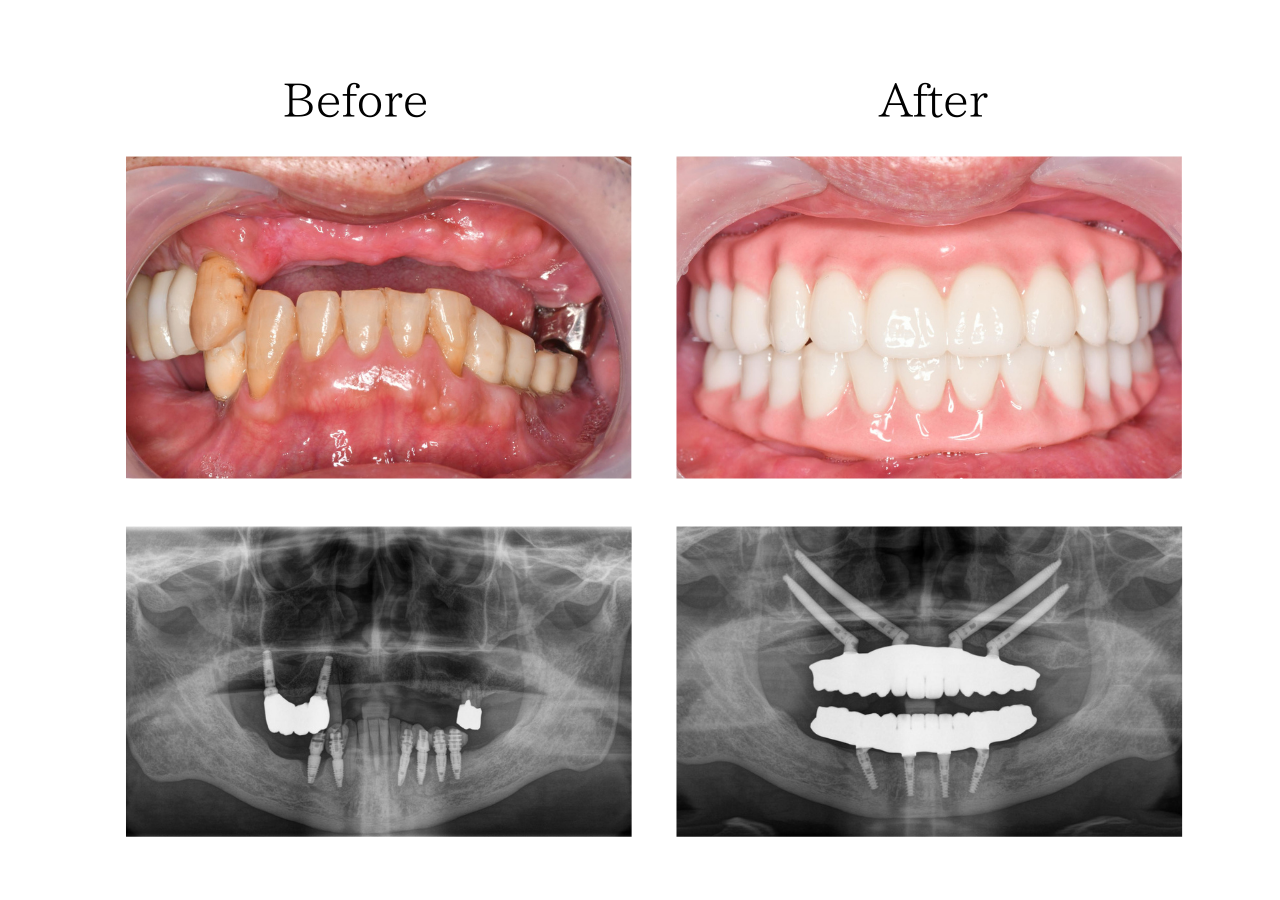

オールオン4 体験談

※上下顎オールオン4ザイゴマ

※費用:4,925,000円*モニター価格

※期間:半年

※リスク:出血、痛み、腫れ、しびれ

「入れ歯を卒業し、固定式の歯にしたい」

60代 男性(佐賀)の場合

上下入れ歯を使用していましたが取り外しが面倒なうえ、入れ歯自体も合わず痛みがあり満足に食事もできなかったです。何度通っても治らない治療にも嫌気がさし、全部一気にできる治療はないかと調べたところ、一日で固定式の歯が入るというおおたわ歯科医院のホームページを見て自分が理想としている治療だと思い、相談しました。